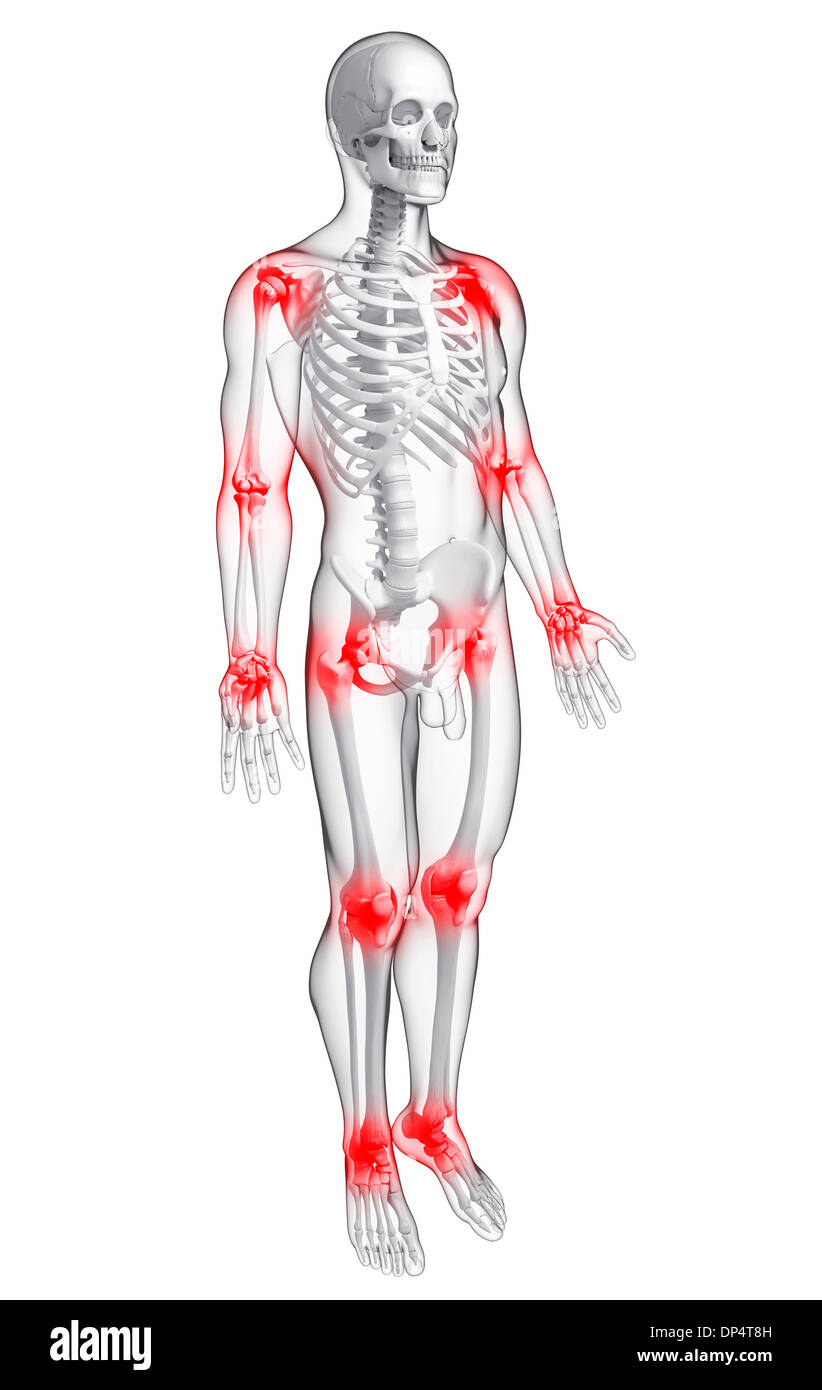

La douleur commune, artwork Banque D'Imageshttps://www.alamyimages.fr/image-license-details/?v=1https://www.alamyimages.fr/la-douleur-commune-artwork-image65260401.html

La douleur commune, artwork Banque D'Imageshttps://www.alamyimages.fr/image-license-details/?v=1https://www.alamyimages.fr/la-douleur-commune-artwork-image65260401.htmlRFDP4T8H–La douleur commune, artwork